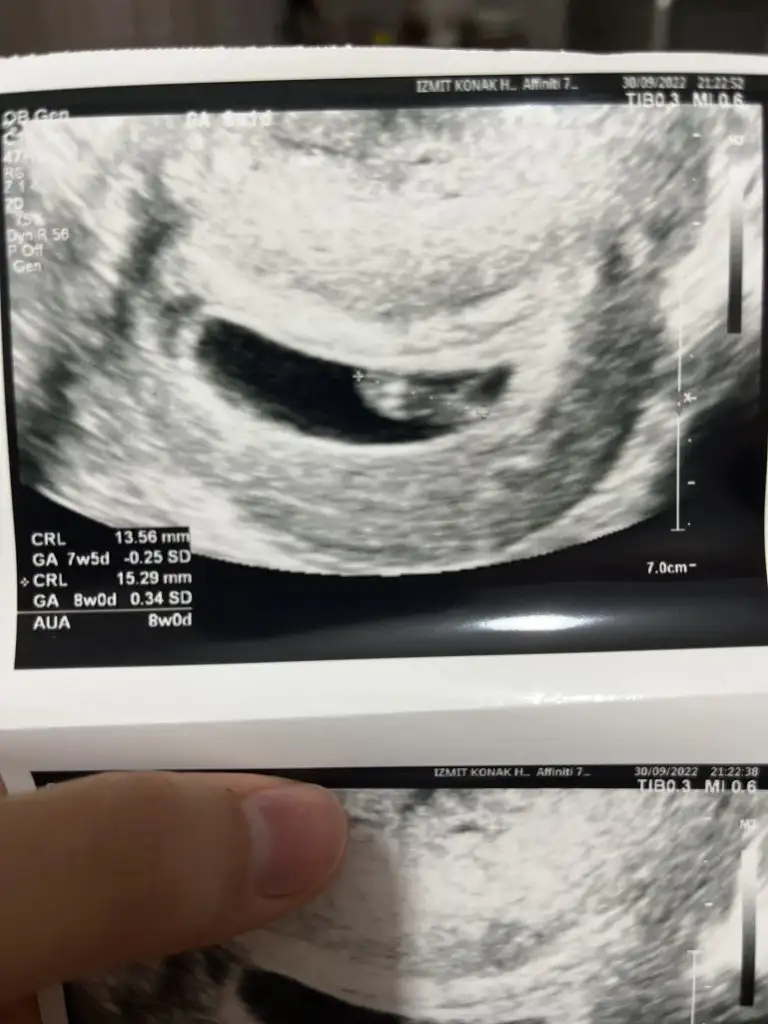

8 haftalık vajinal ultrason ile çekildi yorumlarmısımız çok merak ediyorumSelam Kızlarbir çok kişi gruplardan beni bilir. Yine yetiştim imdatlara

Merhaba cinsiyeti ne oldu bebeğinizin acaba8+1 vajinal ultrason yorum yaparsanız sevinirim teşekkür ederim